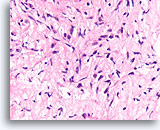

Invasief lobulair carcinoom, Borst FNA, Celblok.

Dunne strengen met lobulaire carcinoomcellen infiltreren het vetweefsel.

40X

Invasief lobulair carcinoom, Borst FNA, Celblok.

Dunne strengen met lobulaire carcinoomcellen infiltreren het vetweefsel.

40X